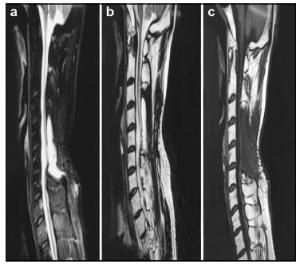

20170512093715  Figure 4 a–c. Postoperative MR images of Case 2.